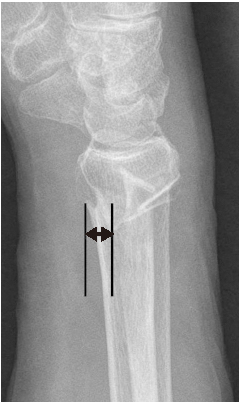

도수 정복 이후 측정한 원위 요골의 영상학적 인자들이 ‘허용 가능한 각도’의 범위일 경우에만 보존적 치료를 시작하였다. 요측 전위 정도는 손목의 전후방 X-ray 사진에서 원위 요골 골편의 요측 이동 정도를 의미한다(Fig. 1). 전후방 전위 정도는 손목의 측방 X-ray 사진에서 원위 요골 골편의 전후방 이동 정도를 의미한다(Fig. 2). 배측 피질골 파절 각도는 원위 요골 골편의 후방 피질골과 요골의 장축이 이루는 각도라고 정의하였다. 배측의 분쇄가 심한 경우에는 단순 방사선 영상에서 가장 뚜렷하게 관찰되는 후방 피질골을 기준으로 각도를 측정하였다(Fig. 3). 수배측 분쇄 골절은 측방 X-ray 사진에서 원위 요골의 수배측에 별개의 골절편(free-floating bony fragment)이 존재하는 경우로 정의하였다(Fig. 4).18) 모든 영상학적 인자들은 도수 정복 전의 초기 단순 방사선 사진 또는 컴퓨터 단층촬영 영상을 토대로 측정되었다. 본 연구는 본원 기관생명윤리위원회(Institutional Review Board, IRB)의 승인(IRB No. 2022-01-013)을 받아 시행한 연구로, IRB에 의해 환자 서면동의서 획득은 면제되었다.

Fig. 1

Radial translation is defined as the distance of the radial side movement of the distal fragment in the anteroposterior radiograph of the wrist. The black lines are perpendicular lines that pass the most ulnar point of the radial cortex of the distal fragment and the most radial point of the radial cortex of the proximal fragment. A double-headed arrow indicates the radial translation.